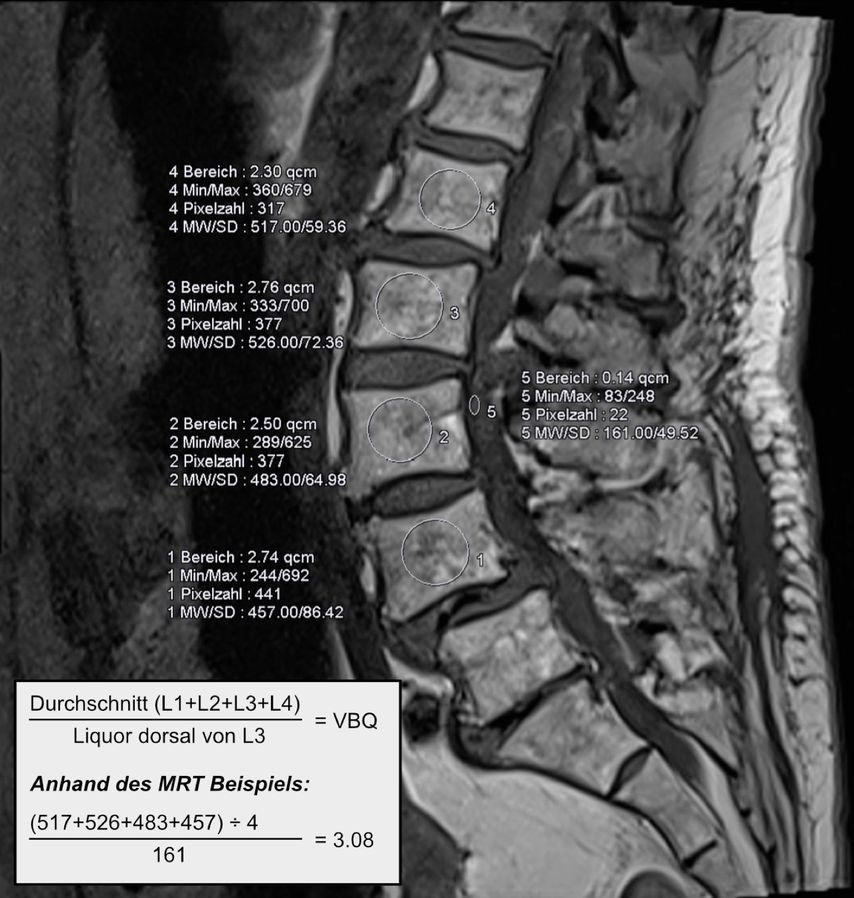

Durch den reduzierten Knochenumbau bei osteoporotischen Patient:innen kommt es auch zu einer verlangsamten knöchernen Fusion, wodurch nicht nur die Risiken für Schraubenlockerungen, sondern auch für Cage-Sinterung (Abb. 2) und Anschlussfrakturen erhöht sind.4, 21 Ein klarer Vorteil für ein bestimmtes Cage-Material dürfte nicht vorliegen. Cages aus Polyetheretherketon (PEEK) oder 3D-Druck versuchen, das Elastizitätsmodell des Wirbelkörpers zu spiegeln. Manche Studien deuten darauf hin, dass reine Titanimplantate eine höhere Sinterungsrate aufweisen als Implantate aus PEEK oder 3D-Druck.25 Viel mehr scheint die Implantatpositionierung und -größe eine Rolle zu spielen. Je mehr Kontakt zur Endplatte besteht, d.h., je größer das Implantat ist und je satter es anliegt, desto eher werden Druckspitzen vermieden und damit das Risiko für Sinterung reduziert.26

Abb. 2: Erhöhtes Risiko für Cage-Sinterung und Anschlussfrakturen durch reduzierten Knochenumbau